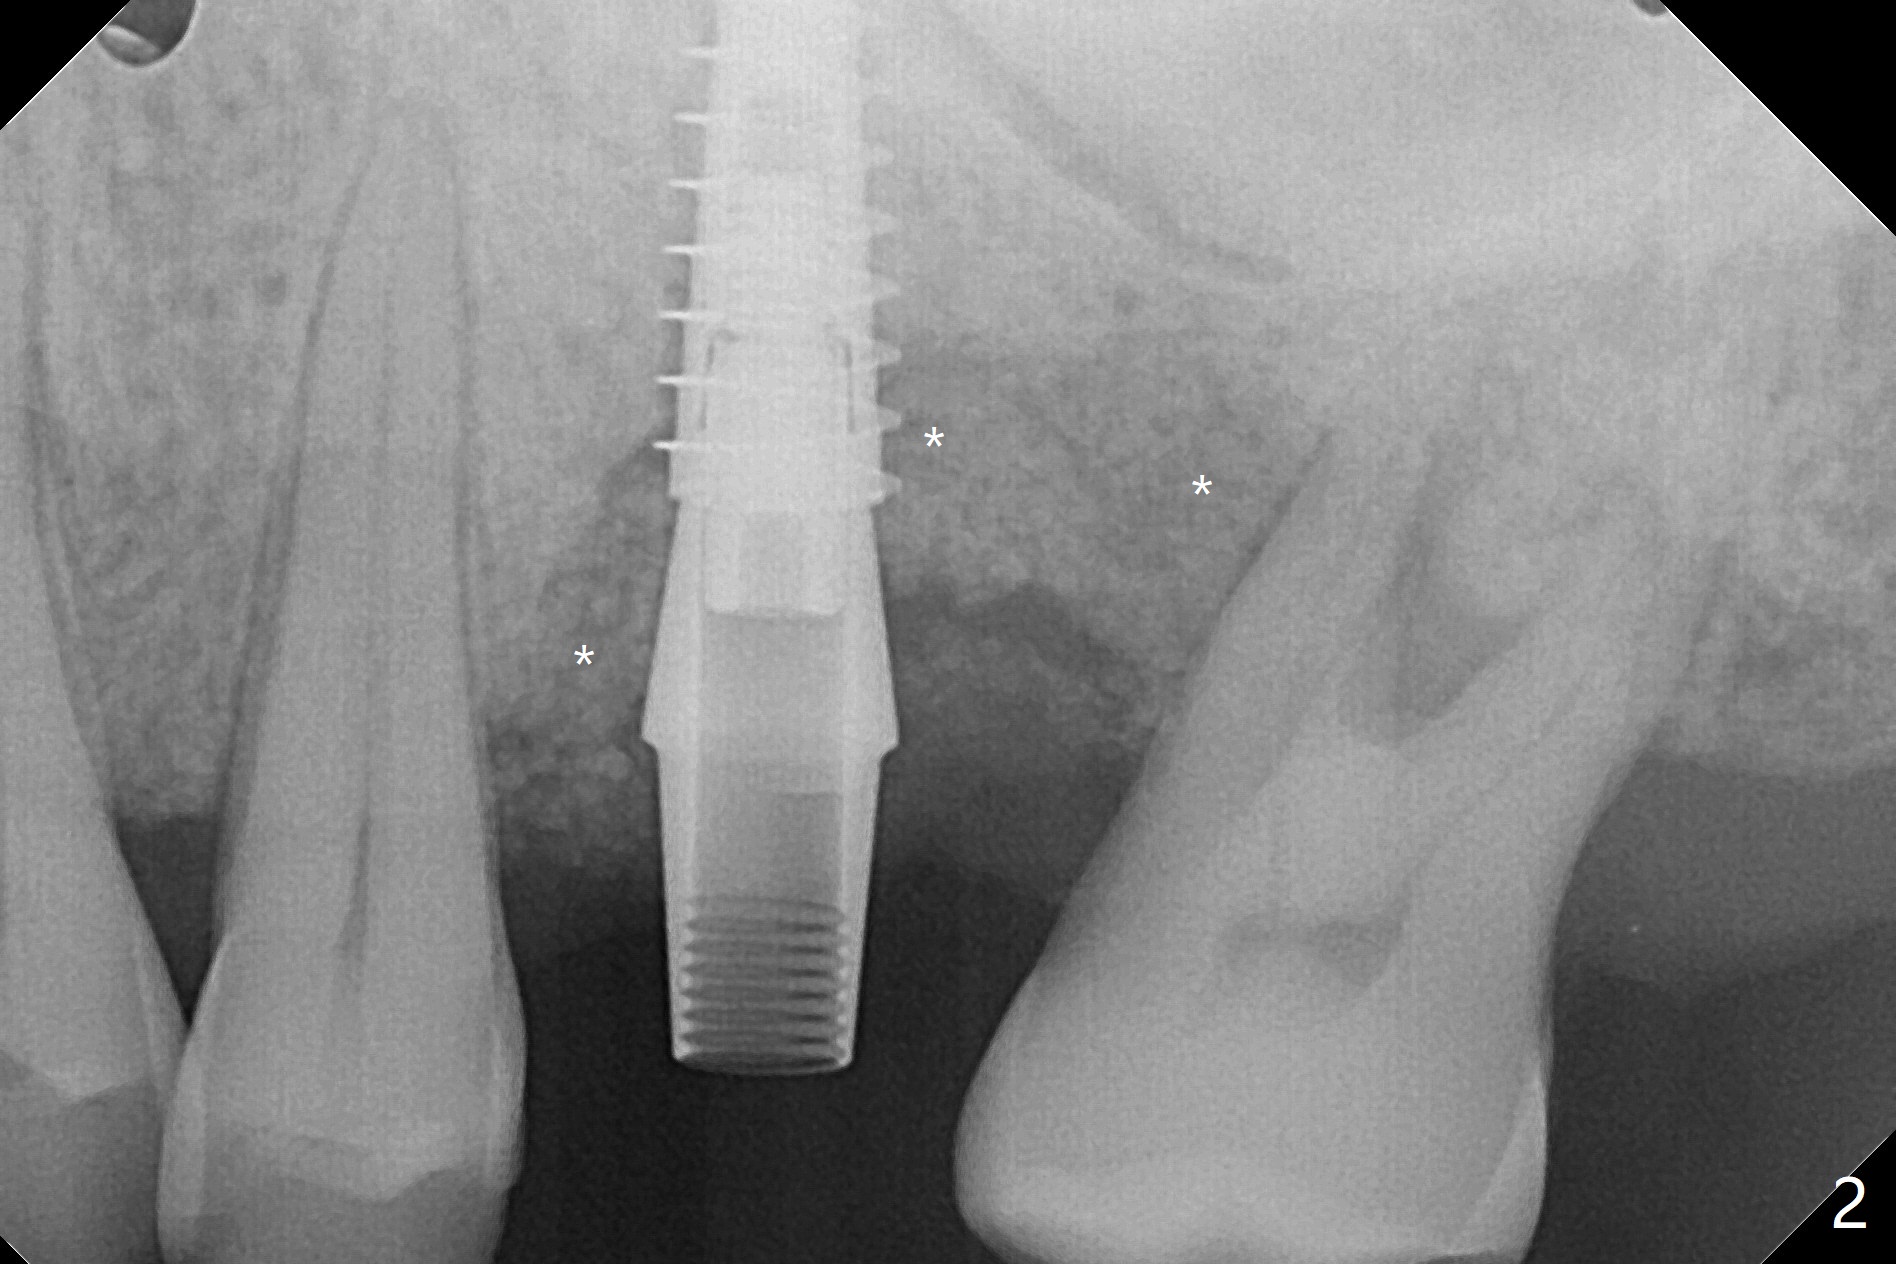

50岁男左上6严重斜型骨质吸收(意味着牙龈特别厚,有可能植入许多骨粉),拔除近中残根后,切开翻瓣,利用导板,4.5x11毫米植体不仅有意近中植入(补偿斜型骨质吸收而造成远中偏移),而且种得表浅(避免使用异常长的基台,改善冠根比例,图一),之后堆入不少粘性骨粉(图二:*),覆盖PRF膜,减张缝合(挺困难),牙周敷料。术后两周,敷料脱落,伤口裂开,但愿骨粉丢失不会太多(图三,四),树脂敷料可能更稳当。术后4个月骨粉好像覆盖远中曾经暴露螺纹(图五:^)。术后四个月伤口愈合(图六),临时牙冠大约3个月。粘固前局部牙龈健康,螺丝扭力30 Ncm。